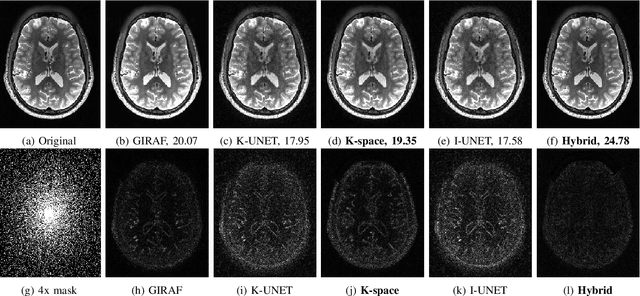

Abstract:We introduce a fast model based deep learning approach for calibrationless parallel MRI reconstruction. The proposed scheme is a non-linear generalization of structured low rank (SLR) methods that self learn linear annihilation filters from the same subject. It pre-learns non-linear annihilation relations in the Fourier domain from exemplar data. The pre-learning strategy significantly reduces the computational complexity, making the proposed scheme three orders of magnitude faster than SLR schemes. The proposed framework also allows the use of a complementary spatial domain prior; the hybrid regularization scheme offers improved performance over calibrated image domain MoDL approach. The calibrationless strategy minimizes potential mismatches between calibration data and the main scan, while eliminating the need for a fully sampled calibration region.

Abstract:Structured low-rank (SLR) algorithms are emerging as powerful image reconstruction approaches because they can capitalize on several signal properties, which conventional image-based approaches have difficulty in exploiting. The main challenge with this scheme that self learns an annihilation convolutional filterbank from the undersampled data is its high computational complexity. We introduce a deep-learning approach to quite significantly reduce the computational complexity of SLR schemes. Specifically, we pre-learn a CNN-based annihilation filterbank from exemplar data, which is used as a prior in a model-based reconstruction scheme. The CNN parameters are learned in an end-to-end fashion by un-rolling the iterative algorithm. The main difference of the proposed scheme with current model-based deep learning strategies is the learning of non-linear annihilation relations in Fourier space using a modelbased framework. The experimental comparisons show that the proposed scheme can offer similar performance as SLR schemes in the calibrationless parallel MRI setting, while reducing the run-time by around three orders of magnitude. We also combine the proposed scheme with image domain priors, which are complementary, thus further improving the performance over SLR schemes.

Abstract:We introduce a model based off-the-grid image reconstruction algorithm using deep learned priors. The main difference of the proposed scheme with current deep learning strategies is the learning of non-linear annihilation relations in Fourier space. We rely on a model based framework, which allows us to use a significantly smaller deep network, compared to direct approaches that also learn how to invert the forward model. Preliminary comparisons against image domain MoDL approach demonstrates the potential of the off-the-grid formulation. The main benefit of the proposed scheme compared to structured low-rank methods is the quite significant reduction in computational complexity.